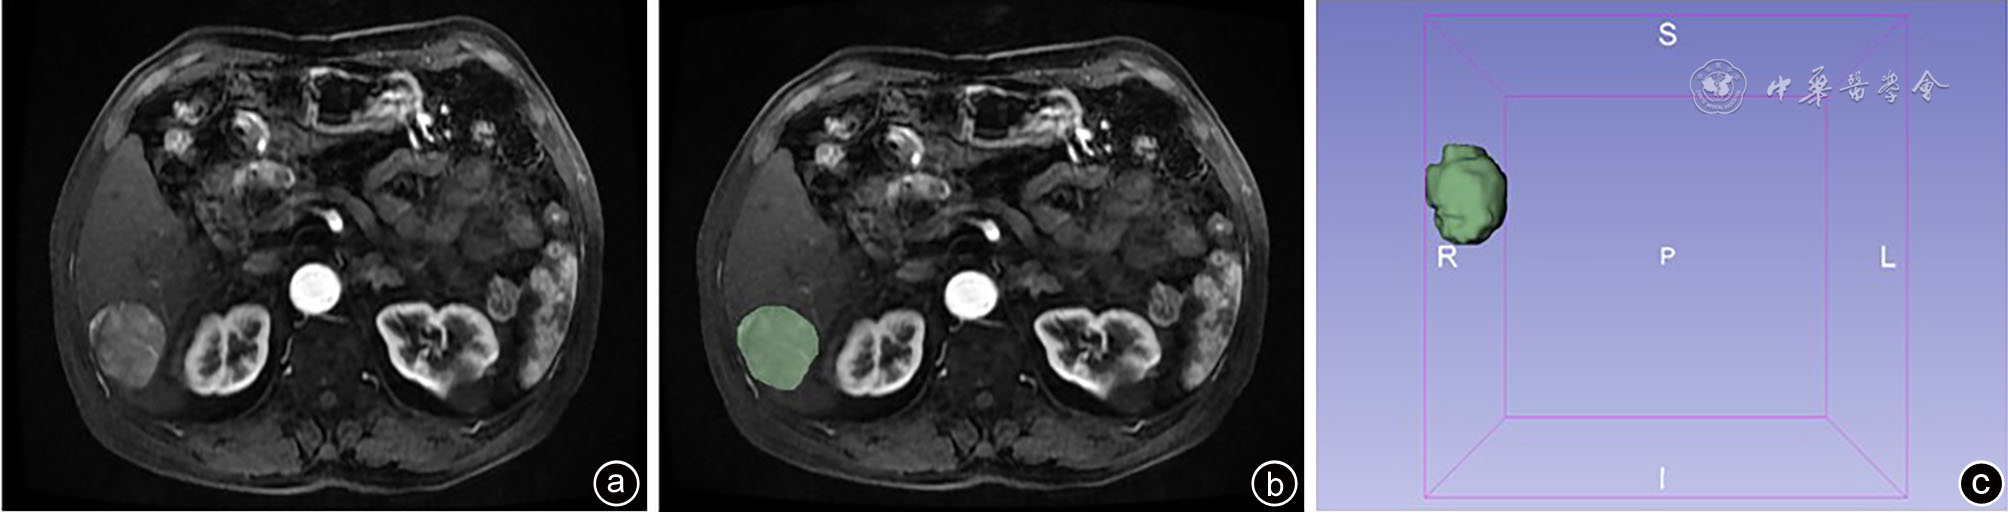

图1 基于肝脏MRI肝癌影像组学分析 注:a、b、c为应用3D-slicer软件勾画ROI;ROI为感兴趣区域